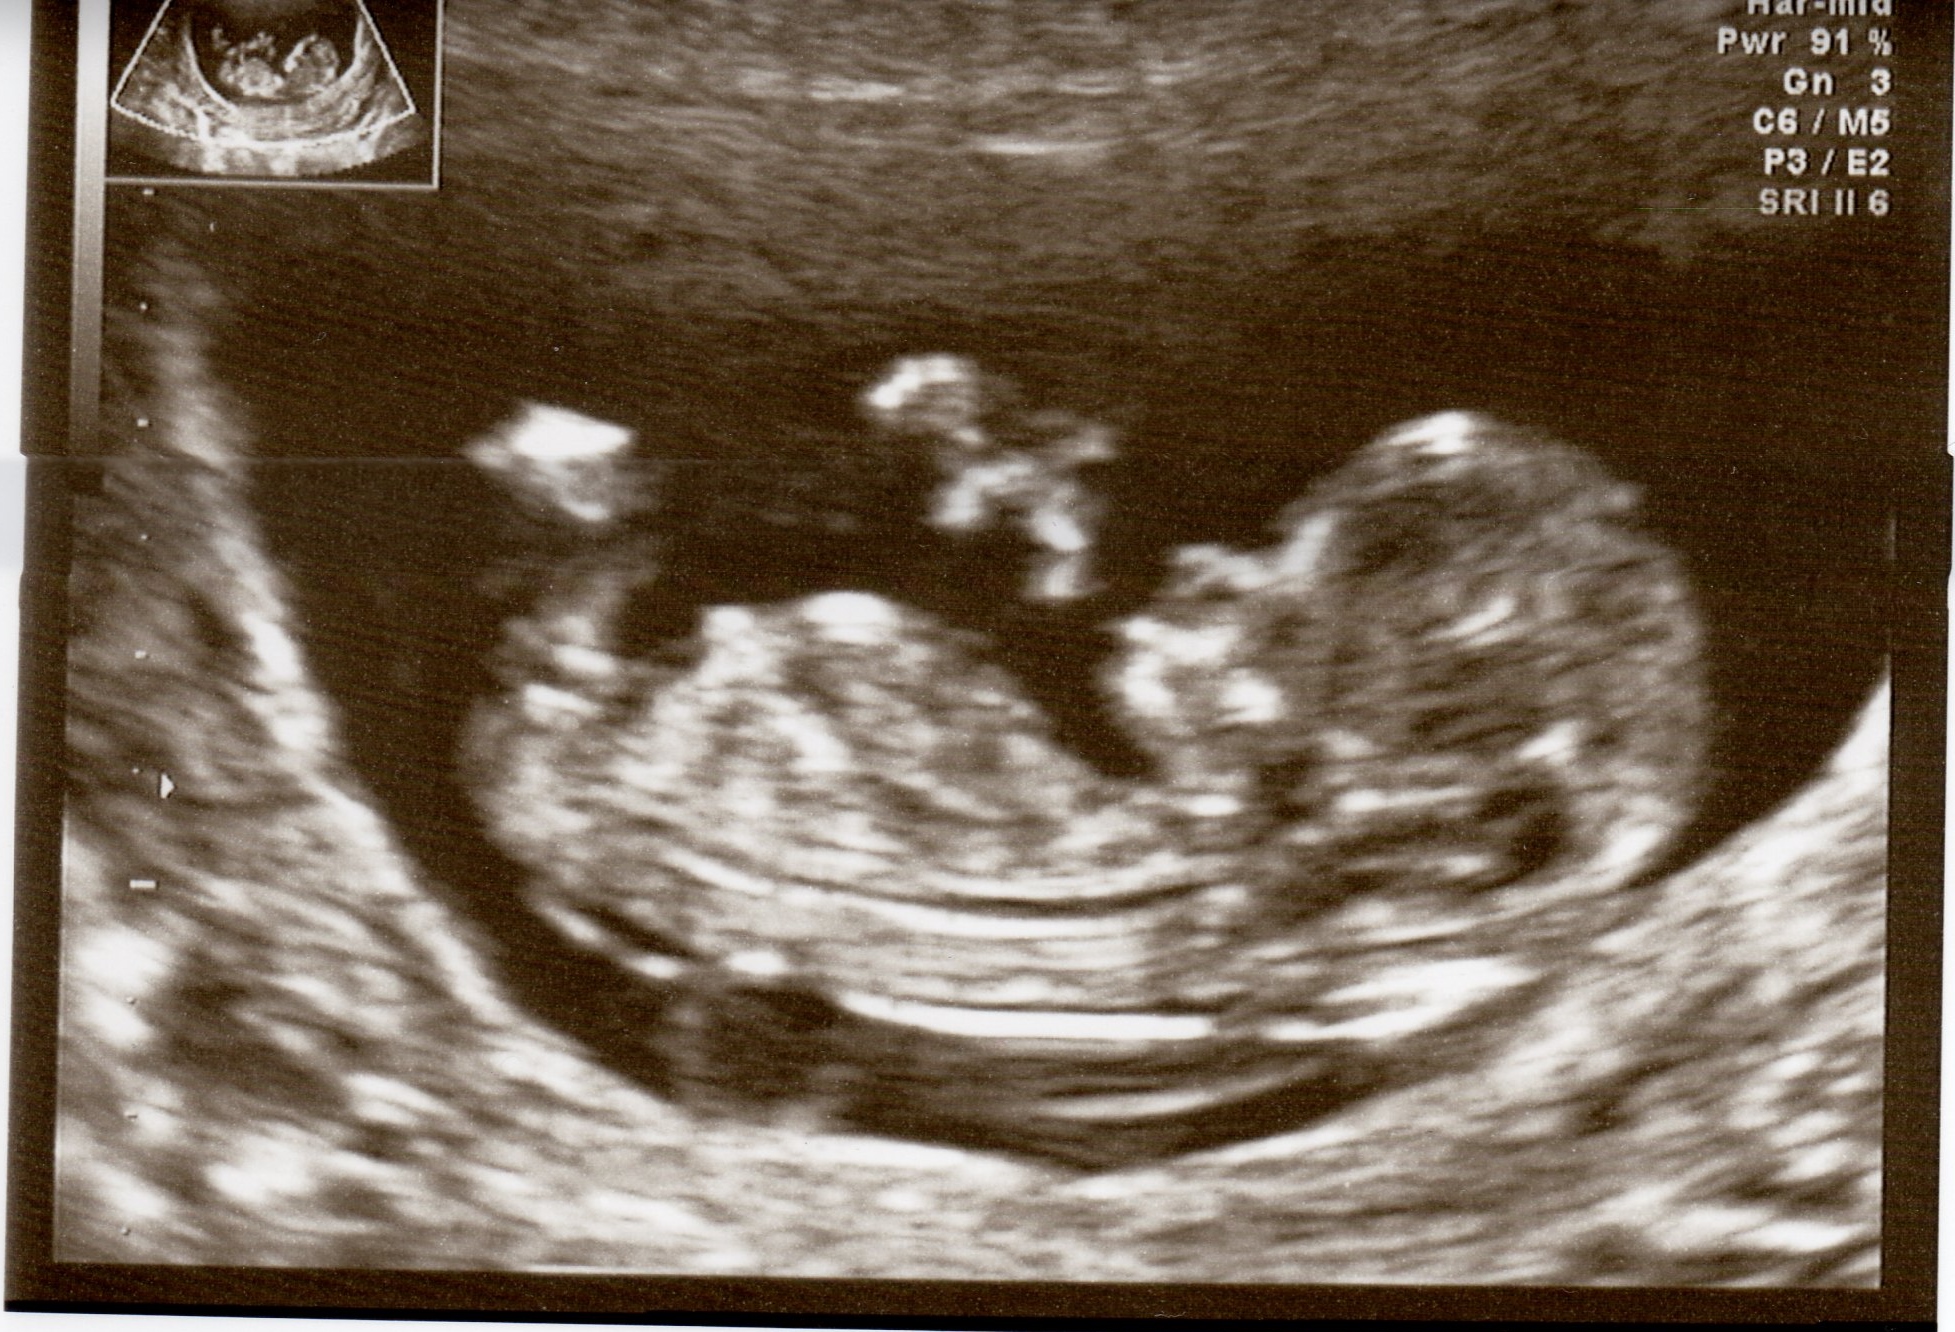

was taken 11 week and 5 days

Too early to tell but at a guess boy

Bit early for an accurate guess but leaning blue

Also guess boy. The nub is on the rise and baby has a flat forehead, and the back of his skull is round.

Skull looks like a boy

Boy guess.